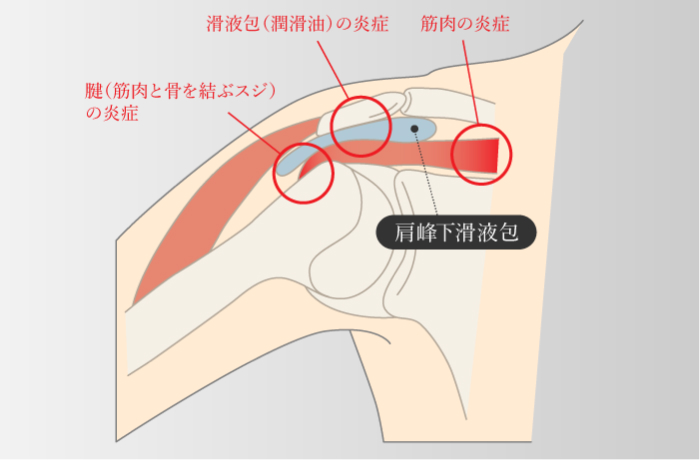

インピンジメント症候群

-

腱板断裂などのはっきりとした損傷を伴わずに肩の痛みを起こす疾患の一つで、肩のこすれや挟まりこみ、骨の衝突などが原因

肩関節周囲炎

四十肩・五十肩

肩関節周囲炎

四十肩・五十肩

-

原因は様々で、関節を構成する骨、軟骨、靱帯や腱などが老化して肩関節周囲の組織に炎症が起きることで可動域制限や痛みが生じる

挙上・外転・結帯・結髪動作の痛み・可動域制限